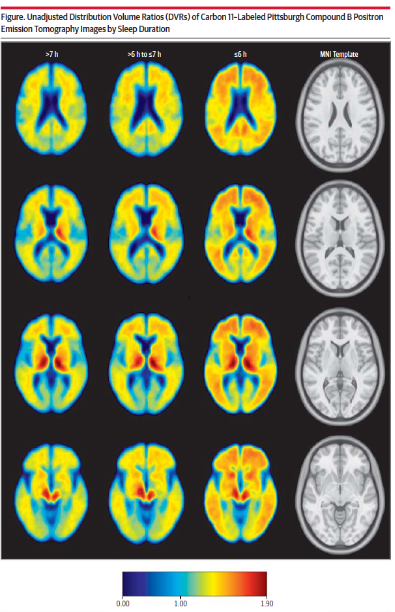

수면 시간이 적고, 수면의 질이 나빠지면 베타 아밀로이드가 더 많이 축적된다는 것을 영상(PiB-PET amyloid imaging)으로 확인하였습니다. 병인이 뇌에 침착된다는 것을 눈으로 확인할 수 있는 시대가 온 것이죠.

세 번째 칼럼(수면시간이 6시간 이하)으로 갈수록 신호가 붉게 나타나는 것이 베타 아밀로이드의 축적을 보여줌.(JAMA Neurol. 2013)